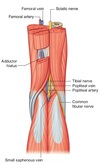

Name muscles A to D

A - Flexor hallucis longus

B - Flexor digitorum longus

C - Tibialis posterior

D - Popliteus